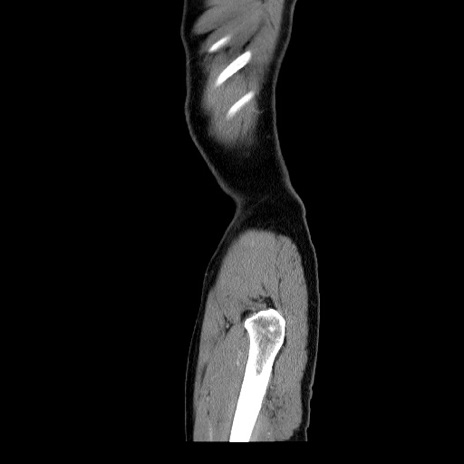

症例34(矢状断像)

【症例】60歳代 男性

【主訴】右鼠径部膨隆

【現病歴】1年程前より右鼠径部膨隆あり。自己にて還納可能だったため放置していた。3時間前より右鼠径部の脱出を認め、還納困難となり受診。

【身体所見】右鼠径部に小児頭大の膨隆あり。弾性硬であり、用手還納は困難。左鼠径部にも膨隆を認める。脱出はなし。